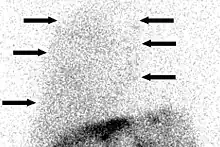

The most noticeable symptoms are usually those of cirrhosis and portal hypertension.[4] Most affected people show signs of end-stage liver disease. Diagnosis involves extracting the fluid via thoracentesis; after this, the fluid is analyzed to diagnose and rule out other causes.[7] The fluid can be analyzed for serum, protein, albumin, lactate dehydrogenase, and cell count. The fluid is a transudate and similar to fluid found in ascites.[4] There may be a higher protein and albumin content in hepatic hydrothorax due to the pleura absorbing the water.[5] To rule out heart-related causes of pleural effusion, an echocardiogram can be performed. Pleuroperitoneal communications are best detected by peritoneal scintigraphy. Hydrothorax without ascites has been reported to occur in as many as 20% of people with cirrhosis but is only detected in 7% of cases via CT scan and ultrasound.[4]